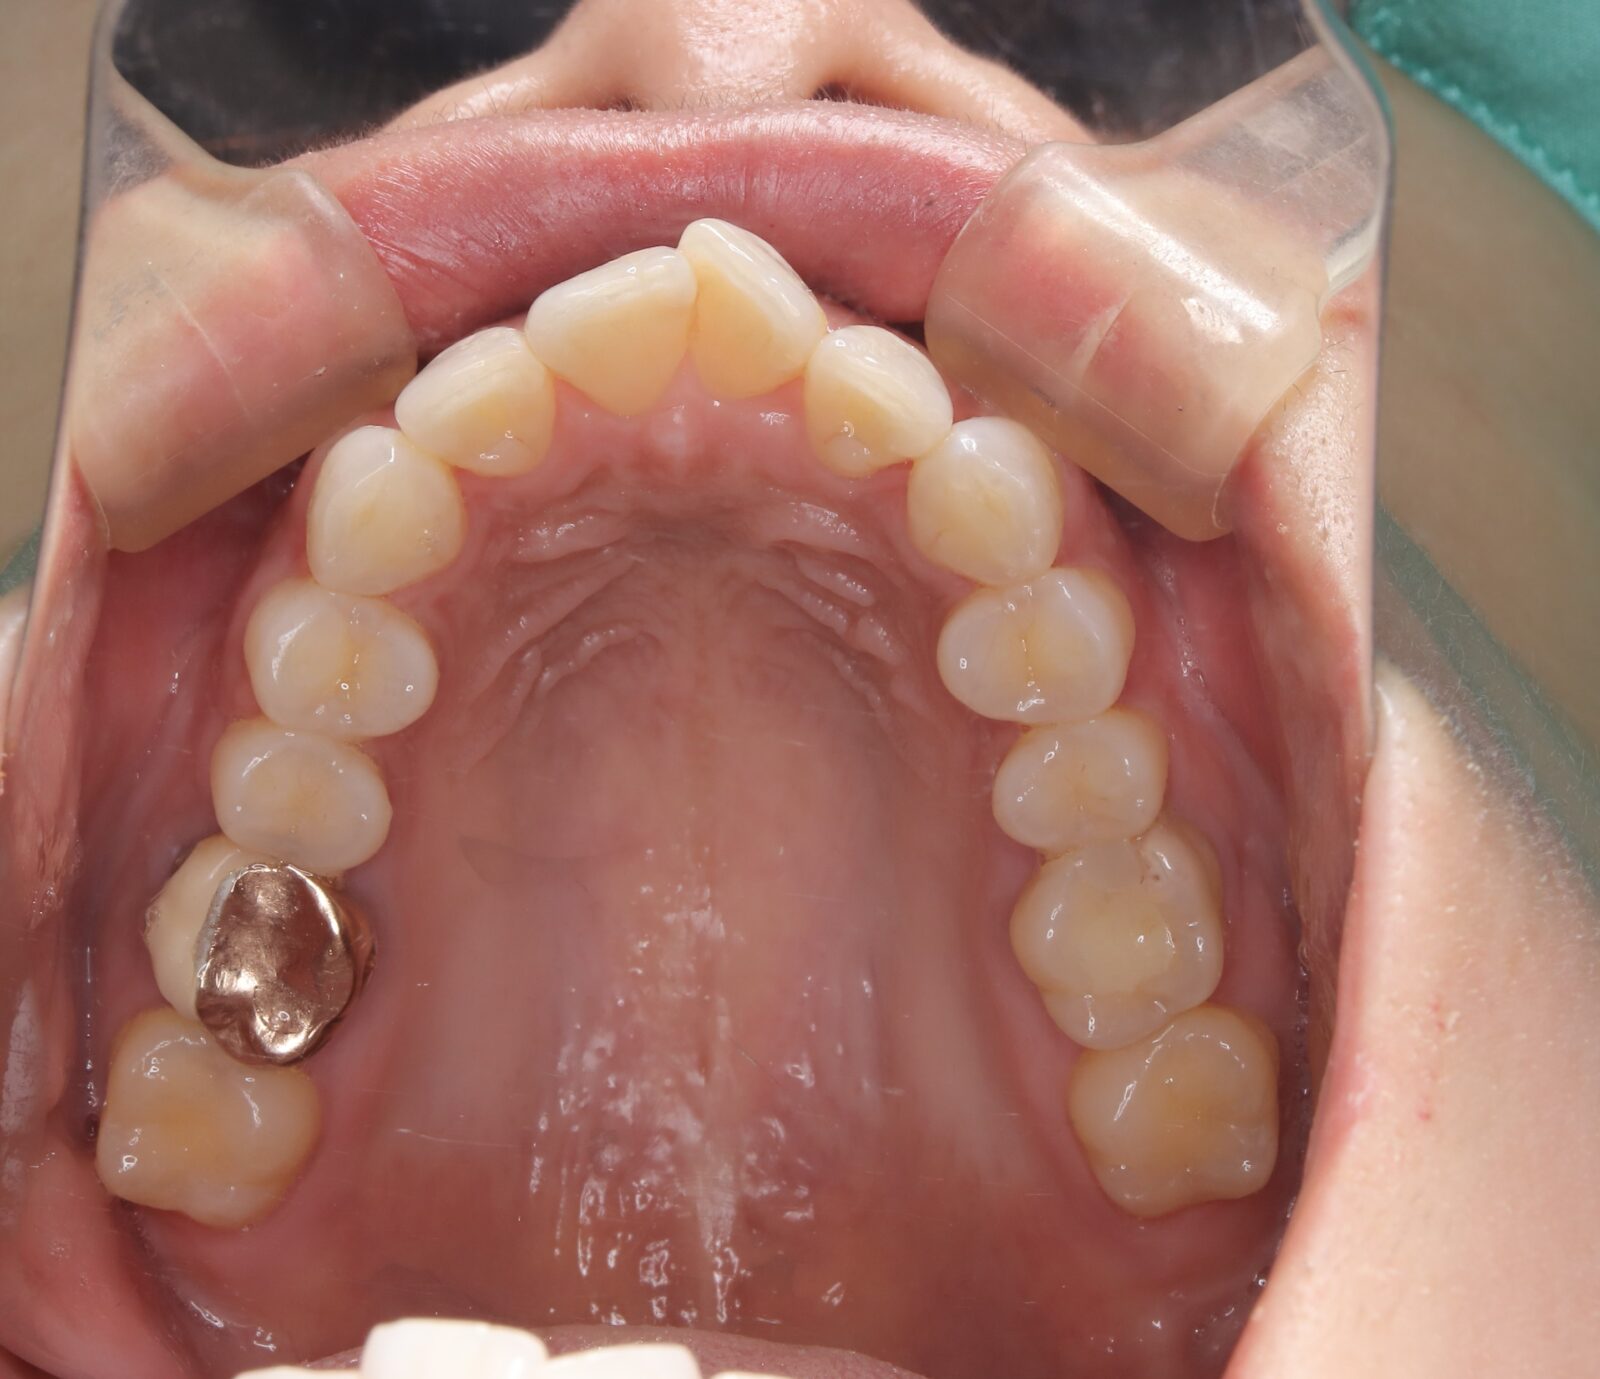

インビザライン(全体矯正)+ホワイトニングコースの症例

歯の裏に歯が隠れてしまっていたため、全体矯正(非抜歯+遠心移動)で美しく改善。

・費用:935,000円(税込)

・治療期間:30ヶ月

・通院回数:30回

・35歳女性

-リスクと副作用-

・長時間マウスピースを装着するため、むし歯や歯周病のリスクがある。治療後はリテーナーを装着しないと後戻りしてしまうリスクがある。

・ホワイトニング剤の影響で知覚過敏が起こる可能性がある。色が徐々に戻る可能性がる。